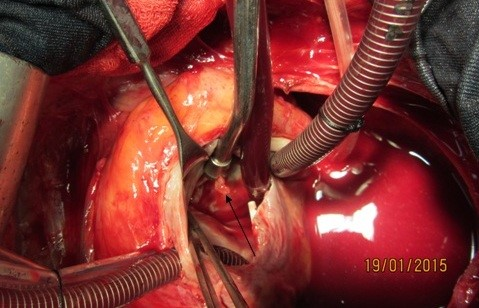

A 37-year-old female patient was referred to our hospital following a full course of Brucella endocarditis in a general hospital for emergency surgery of Brucella endocarditis of aortic and mitral valve. The patient’s past medical history revealed living in endemic area of Brucella infection and a history of consumption of unpasteurized milk products. Her medical history was unremarkable except for sacroiliac arthritis. She had been admitted in a general hospital for assessing fever over the last month. After detecting a positive blood culture for Brucella without its bio-typing, she was treated by following triple combination of drugs consisting of oral rifampin 900 mg per day (qd), oral doxycycline 100 mg twice per day (bid) and gentamicin 80 mg intravenously three times per a day (tid) adjusted with blood levels of drugs and serum BUN and creatinine level. Upon admission, the patient was feverous, tachycardic, her blood pressure was low (80/20), and she had dyspnea. On neurologic examination, the patient was awake and oriented; her skin was cold and damp. The patient’s previous blood cultures at three different times showed a Brucella infection. White blood cell count: 12,000/mm–3 with 70% neutrophils, platelet count: 80,000/mm–3, hemoglobin: 9 g/dl, C-reactive protein: 60 mg/dl, erythrocyte sedimentation rate: 75 mm/h, blood urea nitrogen (BUN): 60 mg/dL, and creatine (Cr): 3.9 mg/dL. Urinalysis revealed no hematuria and 24-hour (diurnal) urinalysis (UA) revealed proteinuria. Serum agglutination tests were positive (titer>1:1,500), and enzyme-linked immunosorbent assay tests for anti-Brucella IgG and IgM antibodies were strongly positive (150 U/ml and 52 U/mL, respectively). A transthoracic echocardiogram (TTE) delineated destruction of mitral and aortic valves by multiple vegetation and multiple small and large aortic ring abscesses extended to surrounding tissue and perforated to right atrium, main pulmonary artery and formation a pocket over the left atrial roof (Figure 1 [Fig. 1], Figure 2 [Fig. 2]). The ejection fraction (EF) was 50% and pulmonary pressure was 60 mmHg. There was severe aortic, mitral and tricuspid valve regurgitation. The patient continued to use the previous anti-Brucella drugs orally while additional evaluations were performed. Due to the patient’s congestive heart failure (CHF) in addition to her multiple mobile aortic and mitral valve vegetation, it was decided that aortic and mitral valve replacement shall be performed immediately. The patient was scheduled for an emergency double valves procedure. However, the night before the surgery, she was intubated due to respiratory distress and was subsequently connected to mechanical ventilator. The patient suffered from severe pulmonary edema caused by CHF that required mechanical ventilation. After intubation, the patient became hypotensive and oliguric needing inotropic drugs use. The patient’s hemodynamic became stabilized and she was taken to the operating room. The intra-operative transesophageal echocardiogram (TEE) did not reveal any new findings. The patient was taken to operating room and a median sternotomy was performed and aortic and bi-cava cannulation was done. After opening the pericardium, it was found that the aortic root was severely attached to the surrounding tissue by inflammatory reaction caused by perforation of abscess in left coronary sinus to roof of left atrium as observed in TEE. The ascending aorta was cross-clamped, and after transverse transaction of the ascending aorta, cardioplegin was indirectly infused to coronaries ostium to induce cardiac arrest. After moderate hypothermic cardioplegic arrest, the umbilical tape was put around both the superior vena and inferior vena cavae and they were snared. The right atrium and left atrium were opened superior and inferior to the atrioventricular groove. Further, intra-operative inspection of right atrium showed small vegetations in crater of fistula entrance to right atrium in antero-medial region of tricuspid ring (Figure 3 [Fig. 3]). However, the tricuspid valve was not involved in infective endocarditis. Intra-aortic root inspection revealed a defect in non-aortic coronary sinus filled with necrotic materials and an abscess that perforated through the area above the tricuspid valve (Figure 4 [Fig. 4]). There was also a fistula between the left-coronary sinus, just near the left coronary ostium to the main pulmonary artery (Figure 5 [Fig. 5]). Further intra-operative perception of aortic root revealed a pocket filled by abscess through a defect in left coronary sinus just located over the roof of the left atrium (Figure 6 [Fig. 6]). In addition to the aforementioned fistulas, multiple vegetations were observed on both mitral and aortic valves that caused severe destruction of both valves causing grave regurgitation (Figure 7 [Fig. 7]). It apeared that mitral valve vegetations were caused by regurgitated aortic valve flow that impinged on aorto-mitral fibrous continuity and subsequently caused the penetration and destruction of the native mitral valve (Figure 8 [Fig. 8]). This infective tissue involved the valve. The abscess was completely debrided to restore and find underlying normal tissue. After debridement of the perforation’s site of the left coronary sinus and cleaning of the performed pocket over the left atrial roof, the aortic defect was repaired by fresh autologous pericardium patch that was used in the external side of the ascending aorta. The fistula tract to main pulmonary artery was closed from intra-pulmonary side of fistula by 4/0 proline sutures, as the closure of small fistula to right atrium. After closing of all three fistula and reconstructing the left sinus of valsalva and replacement of both valves, an oval-shaped fresh pericardial patch was utilized in a sino-tubular junction positioned just close to the superior vena cava, which helped in a tension-free approximation of aortotomy incision. Because the perforation of abscess along the conduction system caused bundle branch block and disturbances of other conduction branches, the atrial and ventricular epicardial pacing wires were used for sequential atro-ventricular pacing. The patient was admitted to the surgical intensive care unit for further control and treatment. Weaning from mechanical ventilation was complicated with tachypnea and grave respiratory distress. Extubation was delayed on the 9th post-operative day after performing a tracheostomy for the better cleaning of respiratory tract secretion and facilitation of extubation. Transient renal and hepatic failure also complicated the postoperative course of surgery. The serum blood nitrogen and creatinine raised to 90 and 5.5 subsequently and was managed accordingly by three times of peritoneal dialysis. Her hepatic and kidney dysfunction recovered relatively in 15th day of operation. A TEE in discharge time revealed a normal functioning of both bioprosthetic valves; however, a mild paravalvular leakage was observed in aortic position. Moreover, correction of all fistulas was successful and no residual flow signal in area of fistula repair was found. She was discharged home on the 25th day after admission.

Figure 4: Vegetation on destructive anterior mitral leaflet (black arrow)

Figure 5: Vegetation in entrance of fistula tract to right atrium in tip of suction (black arrow)